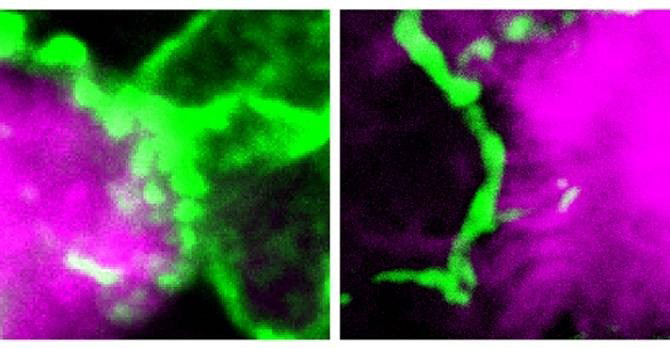

Células inmunitarias llamadas microglías (en verde) pueden ayudar a refrenar el progreso de las placas características del Mal de Alzheimer (en color magenta), limitando los daños generados por estas en las células cerebrales del entorno. (Fotos: Yale University)

Estos investigadores encontraron que las placas en el cerebro de los ratones con esta mutación estaban recubiertas con fibras puntiagudas proyectándose hacia fuera. TREM2 y su equivalente humano, que en su forma mutada aumentan el riesgo de Alzheimer, parecen ser cruciales a la hora de permitir que las microglías acorralen y contengan el progreso de las placas amiloides, limitando por tanto los daños que dichas placas provocan, tal como razonan los autores del estudio.

Las diferencias en la capacidad de las microglías para acorralar a las placas podrían ayudar a explicar por qué algunos individuos con una gran cantidad de placas amiloides nunca desarrollan los déficits cognitivos asociados con el Mal de Alzheimer.